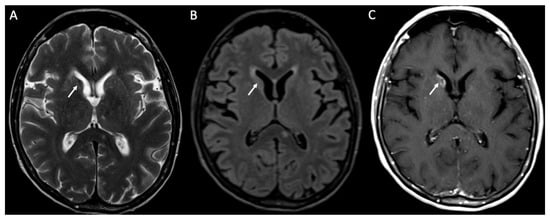

| Herpes Virus type 1 | • Mesio-temporal involvement • Bilateral and asymmetric pattern • Cortical hyperintensity on T2 and FLAIR, with restricted diffusion (acute phase) and cortical enhancement (subacute phase) • Hemorrhagic foci |

| Human herpesvirus type 6 | • Similar to herpes virus type 1, but cortical enhancement is more common |